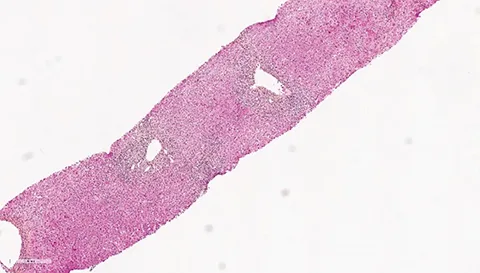

Les patients suivis pour une CBP peuvent présenter des degrés variables d’inflammation hépatique mais habituellement, dans la CBP, on retrouve très peu d’hépatite d’interface ou d’hépatite lobulaire. Environ 8 à 10 % des patients CBP vont présenter des lésions hépatiques faisant évoquer une HAI associée (1, 2). Le syndrome de chevauchement CBP+ HAI peut être présent d’emblée dès le diagnostic initial de la CBP dans 60 % des cas mais les patients CBP peuvent également, dans 30 % des cas, présenter une HAI dite secondaire apparaissant parfois plusieurs années après le diagnostic. Les patients HAI peuvent présenter dans 10 % des cas une CBP dite secondaire (figure 1) (3). Dans le cadre d’une CBP, une augmentation anormalement élevée des transaminases (> 5N) et des IgG (> 20 g/l) doit faire suspecter une HAI associée (4). Des anticorps anti- muscle lisse de spécificité anti-actine et des anticorps anti-ADN double-brin peuvent être présents dans 10 % des cas de CBP. Leur présence doit également faire suspecter l’existence d’un syndrome de chevauchement CBP+ HAI. Dans une étude s’intéressant aux anticorps anti-ADN double brin, ceux-ci étaient présents chez 60 % des patients CBP+ HAI, mais seulement chez 4 % des patients CBP et 26 % des patients HAI (p<0,0001 et 0,01 respectivement). La double positivité d’anticorps anti-ADN double brin et d’anticorps anti-mitochondries était présente chez 47 % des patients CBP+ HAI, mais seulement chez 2 % des pathologies contrôles (5). Dans une autre étude, la présence d’anticorps anti-ADN double brin, une augmentation des ALAT et des IgG étaient les trois facteurs significativement associés aux CBP+ HAI (6). De plus, chez les patients CBP non répondeurs à 12 mois à l’acide ursodésoxycholique (AUDC), une HAI doit être systématiquement recherchée. La présence d’un seul élément évocateur d’HAI n’est en revanche pas suffisant pour poser le diagnostic de syndrome de chevauchement. La réalisation d’une biopsie hépatique, en l’absence de contre-indication, est nécessaire pour confirmer le diagnostic de CBP+ HAI. La présence d’une hépatite d’interface et/ou d’une hépatite lobulaire, bien que non spécifiques, et son intensité permet de confirmer la présence d’une HAI. Le score histologique « modified HAI » (mHAI) développé par Ishak et al. permet de décrire l’activité hépatique inflammatoire et définit les indications de traitement (7, 8). Ce score décrit 4 catégories d’inflammation nécrotico-inflammatoire : l’hépatite d’interface périportale, la nécrose confluente, l’inflammation lobulaire et l’inflammation portale (figure 2). Un score mHAI> 4 est une indication de traitement immunosuppresseur. Les critères de Paris définis par Chazouillières et al. sont cependant les plus couramment utilisés et recommandés par la société européenne pour l’étude du foie (EASL) pour poser le diagnostic de syndrome de chevauchement CBP+ HAI. Ils reposent sur la présence d’au moins deux critères sur trois de CBP : PAL> 2N ou GGT> 5N ; anticorps anti mitochondries≥ 1/40 ; lésions biliaires florides à l’histologie et d’au moins deux critères sur trois d’HAI : ALAT> 5N ; IgG sériques> 2N ou présence d’anticorps anti muscle lisse ; une hépatite d’interface modérée à sévère en histologie (tableau 2, figure 2) (1). Dans une étude publiée en 2010, la sensibilité et la spécificité des critères de Paris pour diagnostiquer une CBP+ HAI étaient respectivement de 92 % et 97 % (9). Le score de Paris est un score différent de ceux utilisés pour faire le diagnostic de chaque pathologie propre CBP ou HAI. Le groupe de travail international de l’HAI ne recommande pas l’utilisation des scores diagnostiques habituels d’HAI (corrigés ou simplifiés) pour faire le diagnostic de CBP+ HAI du fait de leurs très faibles sensibilité et spécificité (9-12). L’objectif de poser un diagnostic de syndrome de chevauchement, et de manière précoce, est de pouvoir proposer un traitement adapté, notamment immunosuppresseur afin d’éviter la progression de la fibrose. Néanmoins, il est important de ne pas porter de diagnostic par excès afin d’éviter aux patients des effets secondaires d’une corticothérapie et/ou d’un traitement immunosuppresseur qui peuvent être sévères.

Figure 2 : Lésions histologiques biliaires évocatrices de CBP (A, B, C), lésions histologiques d’hépatite d’interface et d’hépatite lobulaire évocatrices d’HAI (D, E, F).